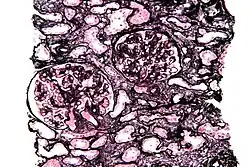

Micrograph of a kidney biopsy stained with a Jones stain.

Jones' stain, also Jones stain, is a methenamine silver–periodic acid–Schiff stain used in pathology.[1] It is also referred to as methenamine PAS which is commonly abbreviated MPAS.

It stains for basement membrane and is widely used in the investigation of medical kidney diseases.

The Jones stain demonstrates the spiked GBM, caused by subepithelial deposits, seen in membranous nephropathy.